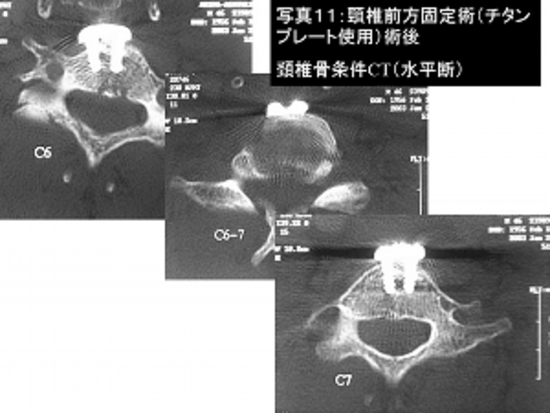

写真11:頚椎骨折(交通事故)に対し前方固定術(チタンプレートを使用)を行いました。

手術後の頚椎CT検査です。チタンプレートを4本のねじでがっちりと固定しております。

患者さんは手術2週間後に歩いて自宅退院されました。